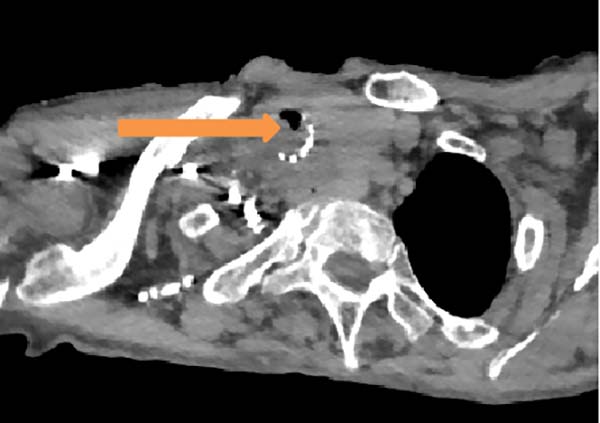

耄耋之年的患者李女士(化名)此前因气道受压曾留置气管支架,尽管原发病治疗取得一定效果,但近两周来喘憋症状反复加重,日常活动及平卧休息均受影响,辗转前来清华大学附属垂杨柳医院胸外科寻求帮助。在接诊后,胸外科团队为患者迅速完善了相关检查,胸部CT及肺功能检测发现患者气道狭窄位置位于原有气管支架旁,因组织增生导致气道严重堵塞。

术前CT(箭头处为气道最狭窄处)